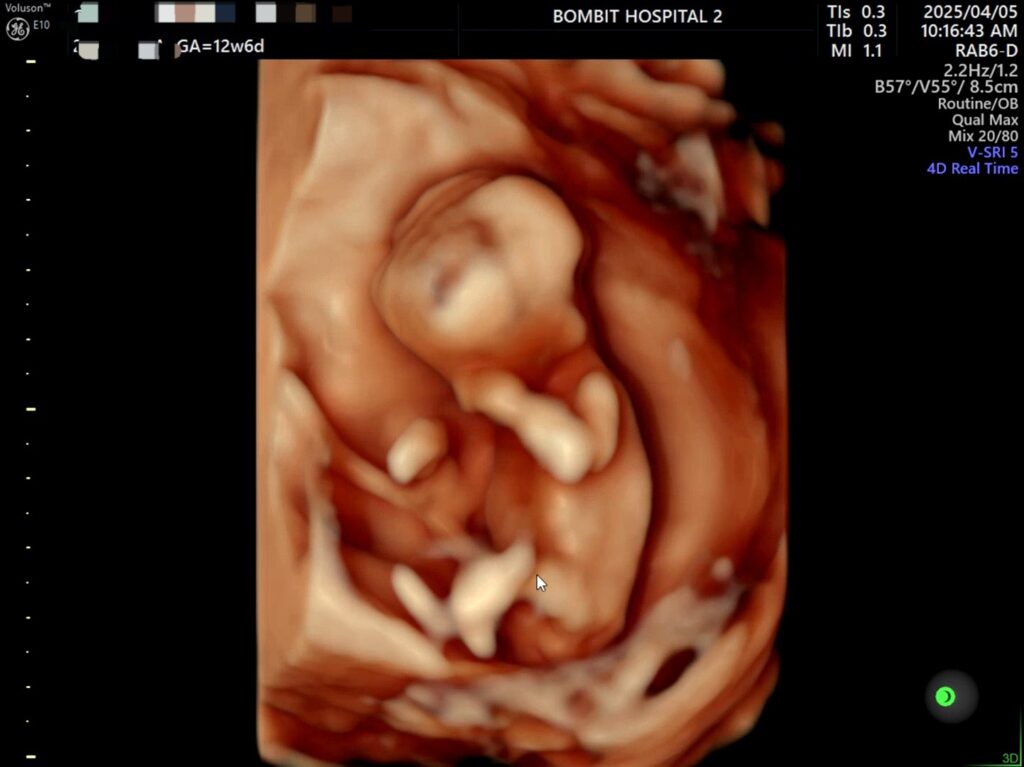

봄빛병원에 다시 방문. 정밀초음파도 하고, 다시 진료도 보았다.

정밀초음파 사진.